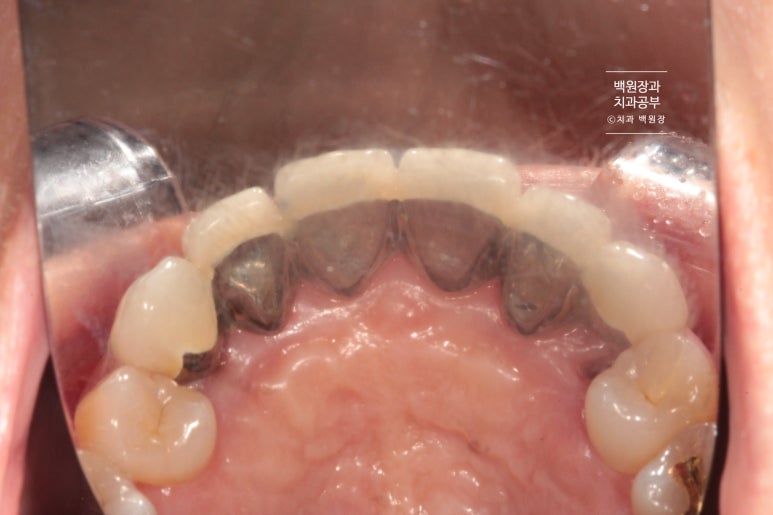

뒤에서 보니 PFM 크라운이었습니다. Porcelain fused metal 이라는 뜻인데요, 메탈 위에 도재를 붙인 형태의 보철물로 옛날에 많이 쓰던 스타일의 보철물이죠.

이렇게 크라운을 여러개 만들 때 가능하면 최대한 낱개로 제작해야합니다. 옛날엔 치과의사의 편의로 붙이는 형태인 splinted crown을 많이 사용했었는데... 치아에도 잇몸에도 아주 안좋은 형태의 보철물이에요!